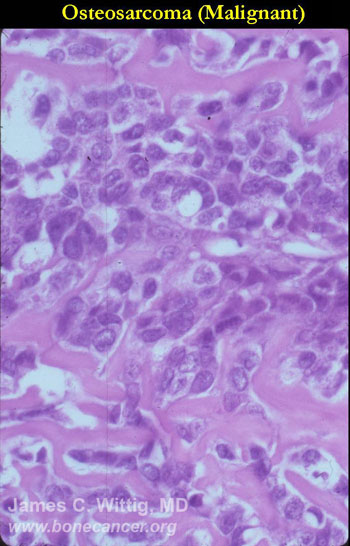

Microscopic Pathology: Conventional Osteosarcoma

- High grade anaplastic tumor

- Hypercellular, spindle cell tumor with extensive pleomorphism (cells are different sizes and shapes)

- Large nuclei and little cytoplasm (high nuclear to cytoplasmic ratio)

- Many mitotic figures and abnormal mitoses

- Bizarre appearing cells with hyperchromatic nuclei

- Osteoid production

- Osteoid is often laid down in lace-like pattern in between the malignant cells

- Osteoid stains pink to red with H&E stains

- No osteoblastic rimming (the cells do not line up on the surface of a trabecula of osteoid as in osteoblastoma or osteoid osteoma)

- Osteoid may or may not mineralize; degree of mineralization determines how visible it is on x-ray

- May have other elements such as cartilage, fibrous tissue, small round blue cells, giant cells and telangiectatic changes

- Fibrosarcoma subtype of conventional osteosarcoma may show spindle cells that arrange themselves in a “herringbone” pattern

- Malignant fibrous histiocytoma (MFH) subtype of conventional osteosarcoma often demonstrates a “storiform” arrangement of cells. There are pleomorphic spindle cells mixed with large, bizarre cells.-

- Giant cell rich conventional osteosarcomas may have large sheets of reactive giant cells that may obscure the underlying sarcoma. Osteoid production may be sparse.

- Preoperative chemotherapy changes the microscopic appearance of conventional osteosarcomas. Necrotic osteoblastic foci appear as acellular osteoid matrix. The cells are killed by the chemotherapy, but the osteoid remains. Fibrosarcomatous areas are replaced by collagen and scar tissue, granulation tissue and inflammatory cells. Chondroblastic foci will have “ghost cells” in lacunae (acellular chondroid tissue)